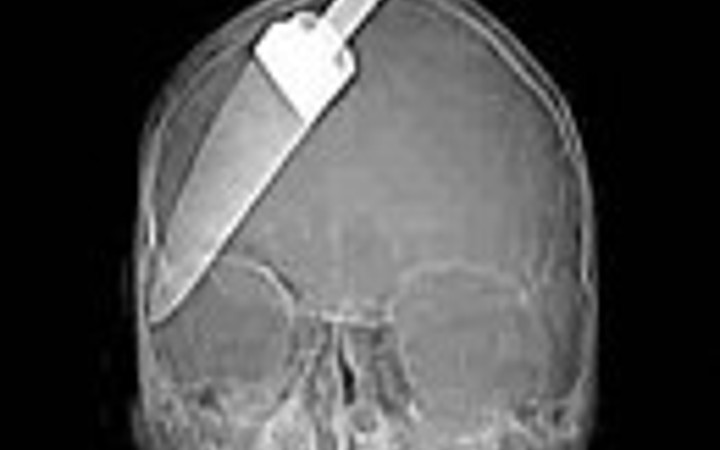

İnanılmaz röntgen filmleri - Resim: 2

İnanılmaz röntgen filmleri görenleri çok şaşırtıyor